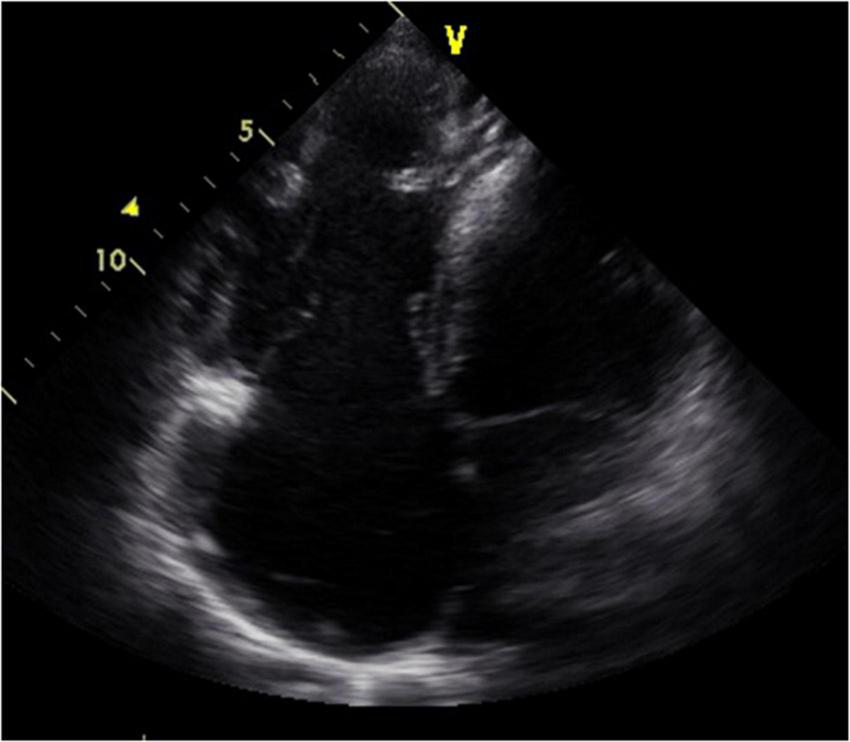

FIGURE 2

Four-chamber view at end-systolic phase of transthoracic echocardiography in Case 1. Note that the tricuspid valve does not close at all, and the right atrium is hugely dilated.